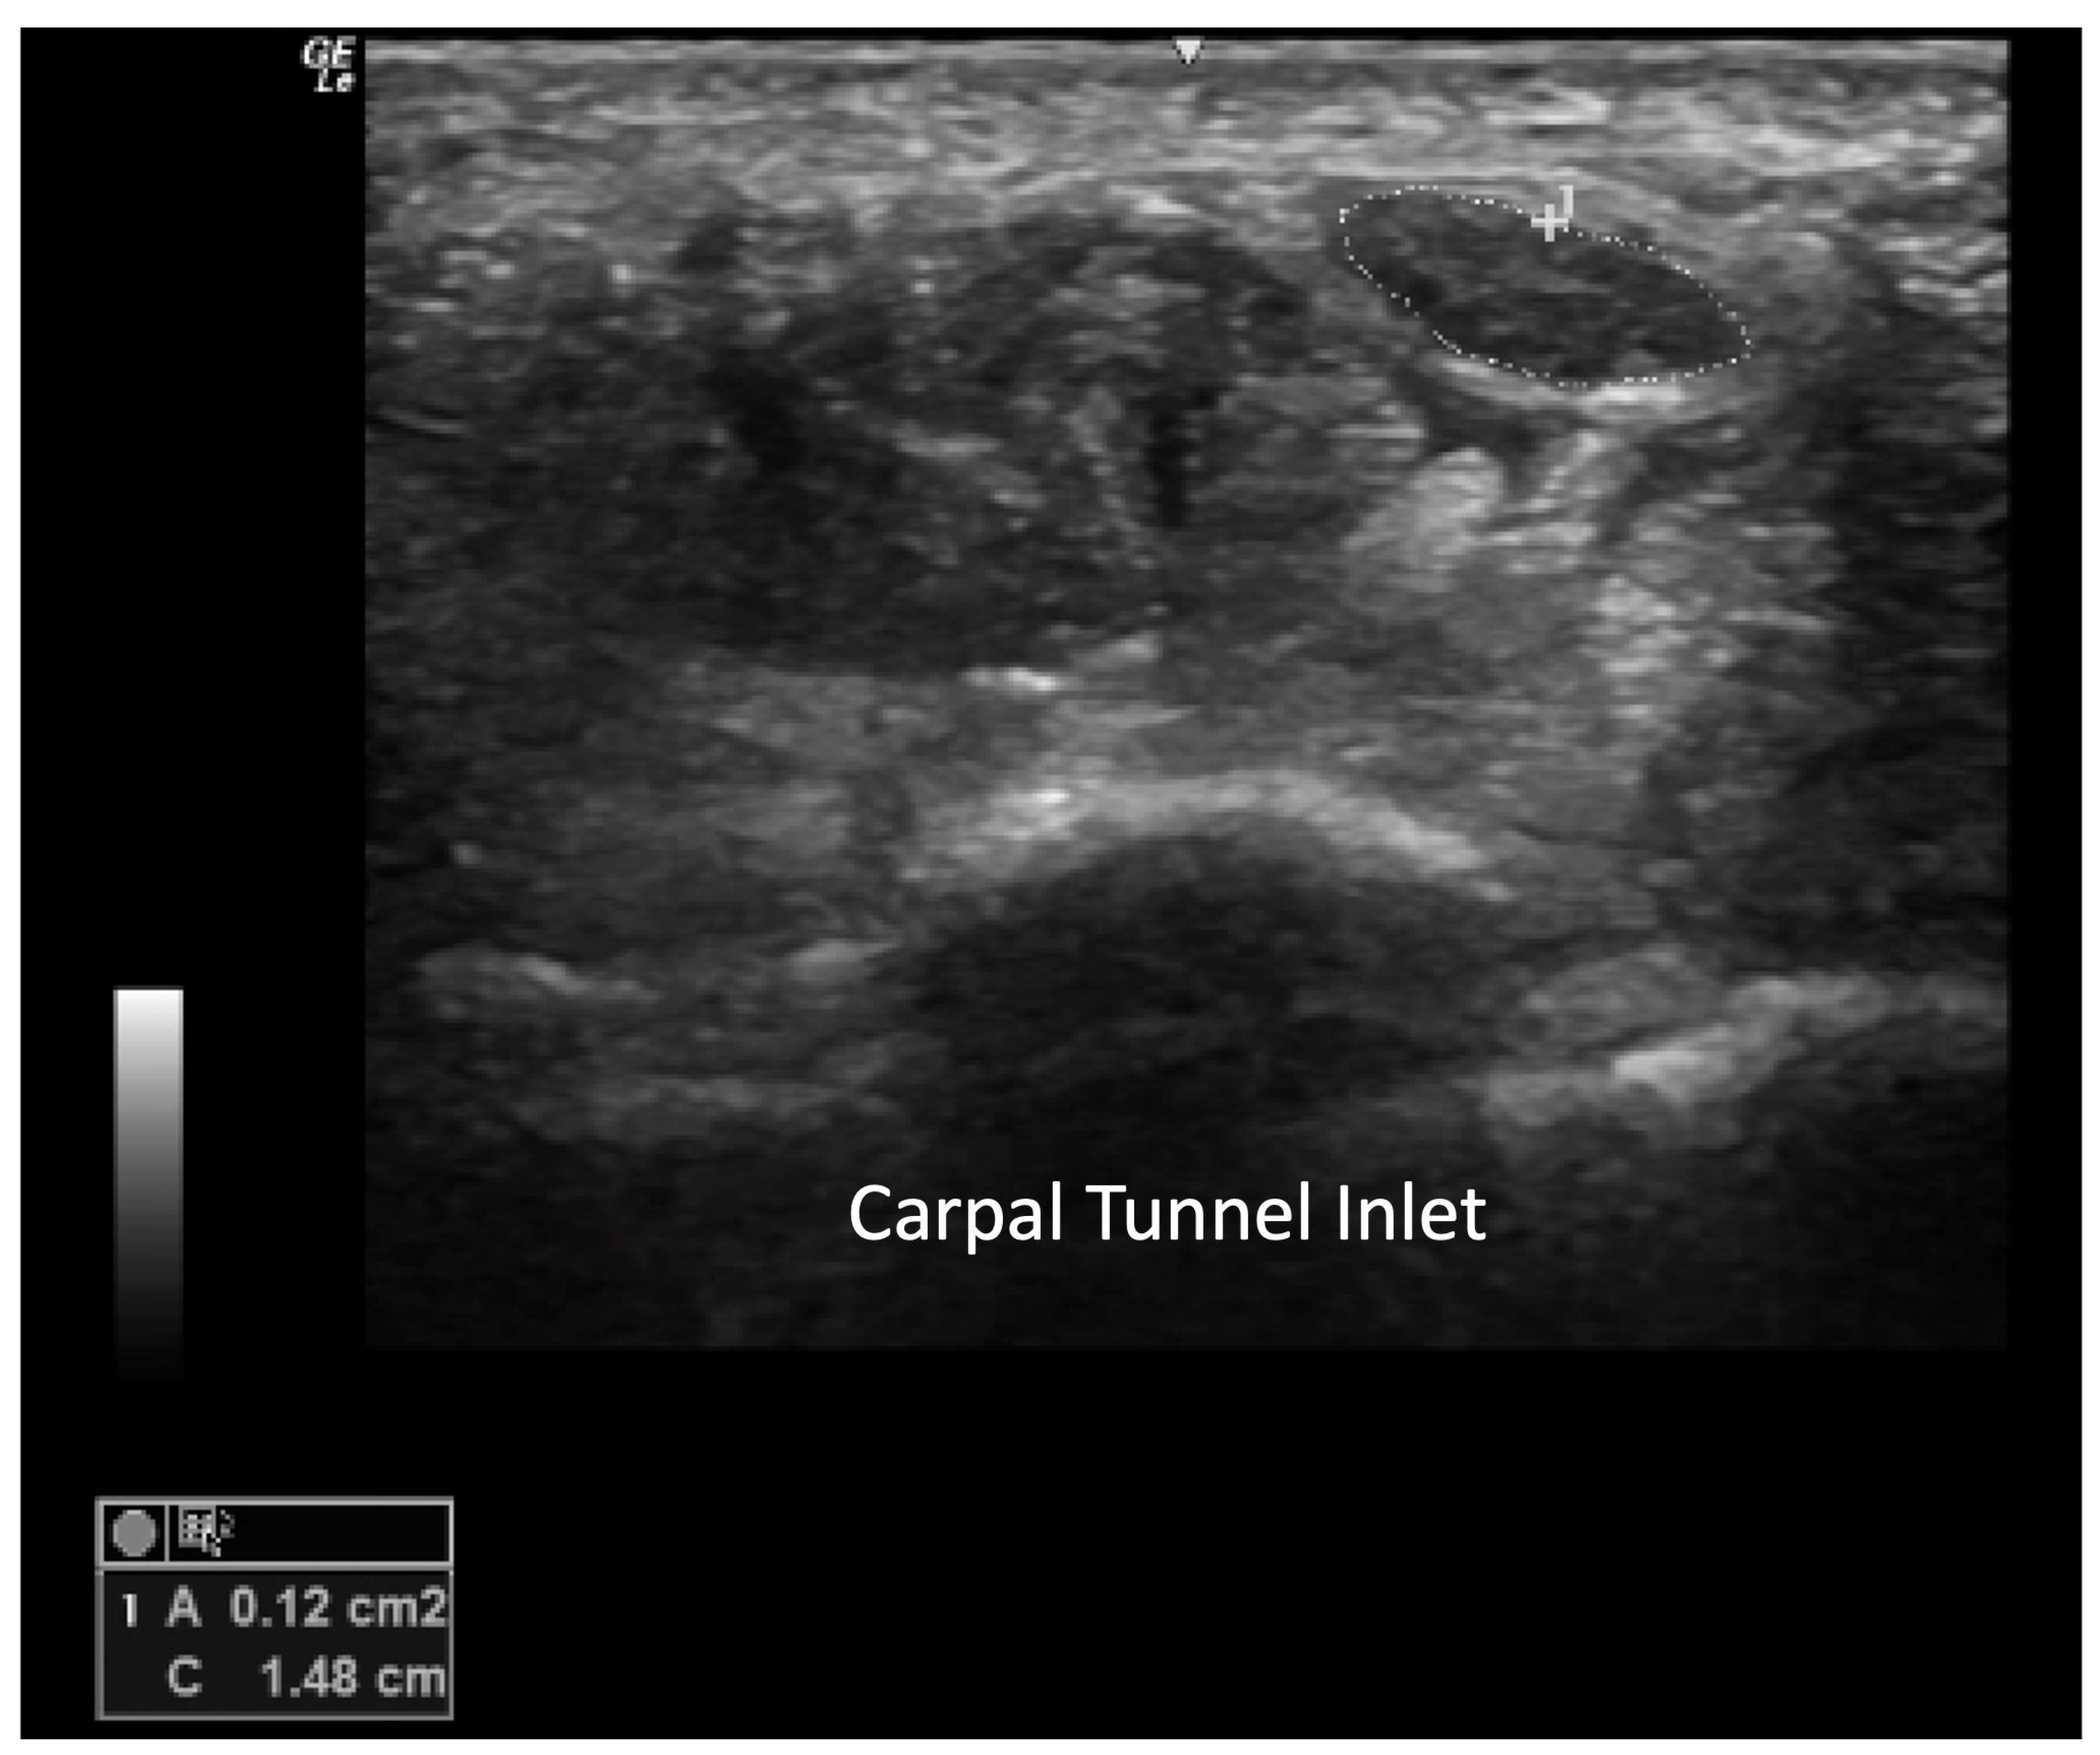

Carpal Tunnel Syndrome

4.2.2. Volar Aspect